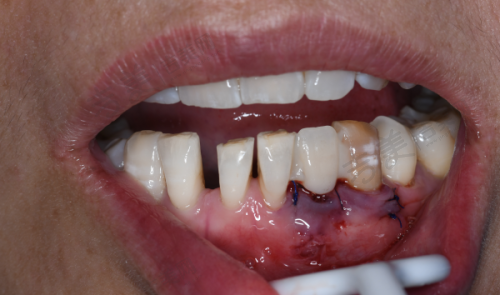

丰富手术项目:上海雅杰口腔诊所诊疗项目丰富,规模适中且科室设置较为齐全。其诊疗科目涵盖口腔科、牙体牙髓病、牙周病、口腔粘膜病、儿童口腔、口腔颌面外科、口腔修复、口腔正畸、口腔种植、预防口腔,还有医学影像科的X线诊断。在手术方面,诊所擅长种植牙手术,无论是前后牙种植,还是内/外提、各类骨增量、穿翼、半/全口即刻种植手术都能熟练开展;牙齿矫正手术也特别出色,包括成人正畸和儿童早期干预;牙齿修复手术同样是其优势,如全口活动义齿修复、美学修复等;此外,在各类阻生智齿拔除、规范化根管治疗、牙周治疗等方面也有丰富的经验和专精的技术。凭借这些优势手术项目,为不同口腔问题的患者提供了有效的治疗方案。

特色科室与项目:上海雅杰口腔诊所的科室设置和特色项目优势明显。科室方面,有口腔科、牙体牙髓病科、牙周病科等多个专精科室。特色项目包括种植牙、牙齿矫正、牙齿修复、儿童牙齿治疗等。种植牙项目采用数字化种植,拥有3D导板种植系统,可精细定位种植位置,减少创伤,修复更快。牙齿矫正中的隐形矫正使用口内扫描仪,5分钟扫描取模,不用咬恶心的石膏,还能即时出3D矫正方案。牙周治疗采用超声波洁牙机 + 激光治疗仪,洁牙更干净,激光消炎减少出血,不适感轻。儿童补牙配备疼痛较小局麻仪 + 卡通牙钻,缓慢给药减少疼痛,卡通造型缓解孩子紧张。这些特色项目凭借精良的设备和专精的技术,为患者提供了优质的口腔治疗体验。